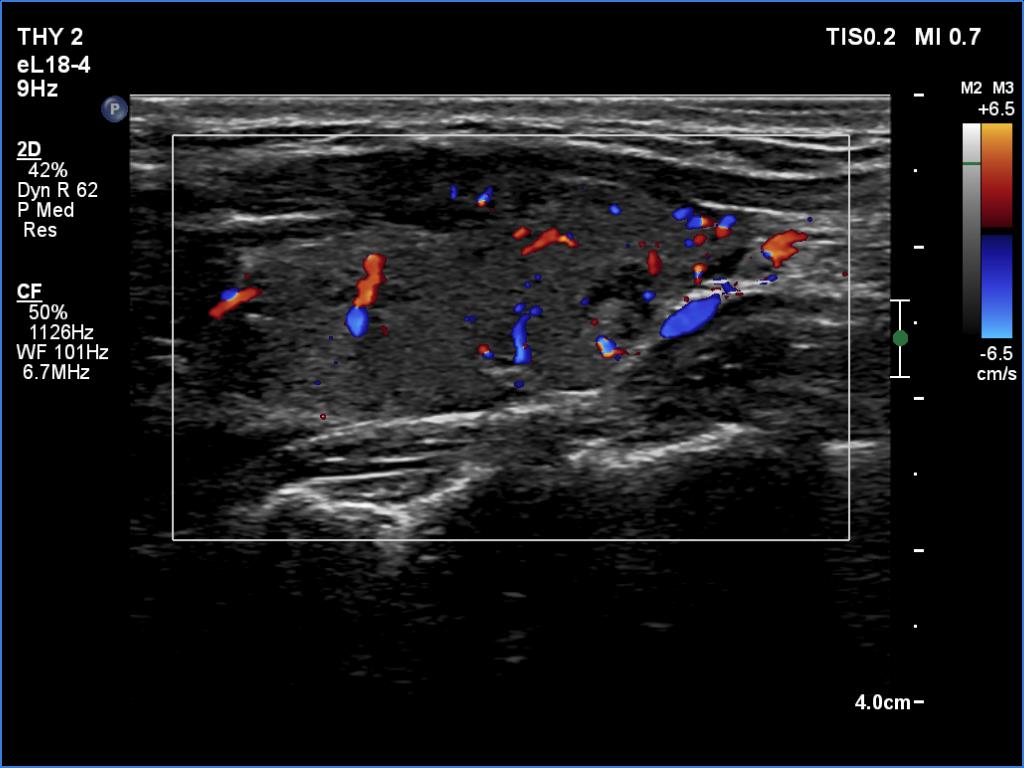

Left lobe, longitudinal view, color Doppler mode. The vascularity is average.